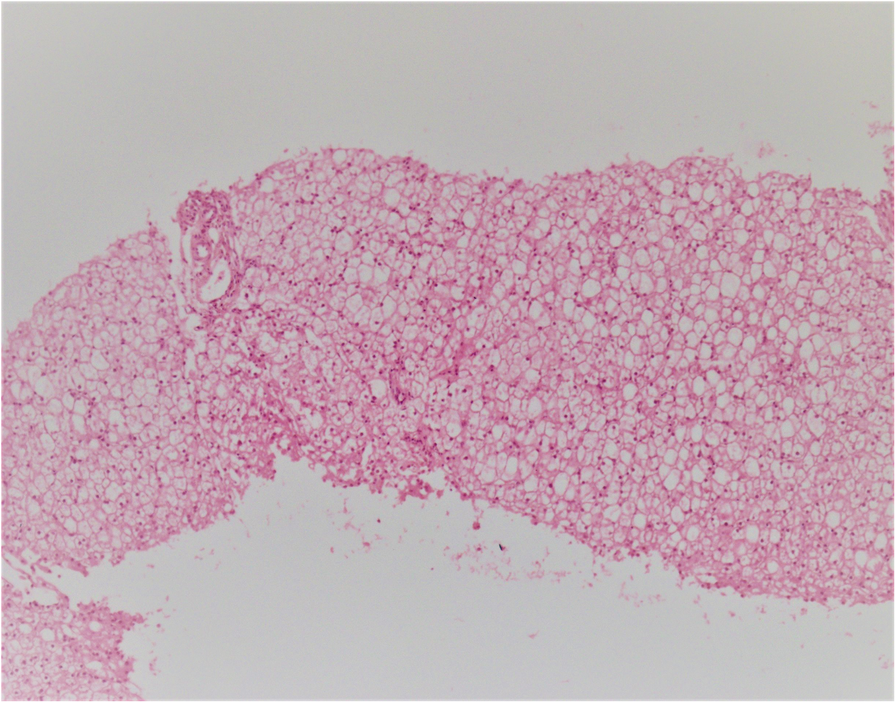

Fig. 1From: Novel mutations in the PHKB gene in an iranian girl with severe liver involvement and glycogen storage disease type IX: a case report and review of literatureSections from liver needle biopsy show distorted architecture with steatosis in the liver parenchyma (very similar to GSD type I)Back to article page